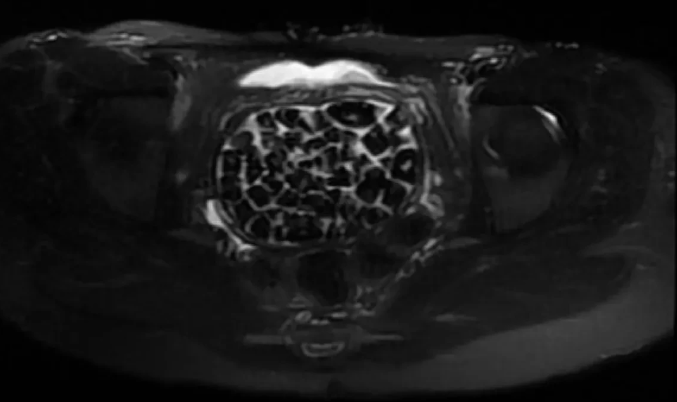

Tedavisi sonrası taburcu edilen genç kız yaşadıklarını anlatırken, operasyonu gerçekleştiren Üroloji Uzmanı Doç. Dr. Erkan Erkan ile Jinekolojik Onkoloji Uzmanı Op. Dr. Emin Erhan Dönmez de nadir olduğunu ifade ettikleri vakaları hakkında bilgi verdi, önemli uyarılarda bulundu. Öte yandan, genç kızın vücudundaki 287 taşın tetkiklerdeki görüntüsü dikkat çekerken taşlar üzerine de incelemeler yapılacak.

Hastasının durumuna yönelik konuşan Üroloji Uzmanı Doç. Dr. Erkan Erkan, "Hastamızın 2004 yılında doğduğunu ardından doğar doğmaz ekstrofi vezika dediğimiz 50 binde bir görülen bir anomaliden dolayı art arda ameliyatlar geçirdiğini öğrendik. 10 yaşında yine bir ameliyat geçirmişti, gerekli görüntüleme ve tetkiklerimizi yaptırdık. Normalde mesanesinin olması gereken yerin hemen arka kısmında taşlarla dolu bir kese olduğunu gördük, bunun üzerine ek görüntülemeler; MR çektirdik. Hastamız çelişkili açıklamalar almıştı, kendi radyolojik kliniğimiz ve edindiğimiz konsültasyonlarda taşların mesanede değil vajinal boşlukta oluştuğunu düşündük, bir planlama yaptık. Kadın doğum hocamızın da çabasıyla taşları tamamen temizledik ardından ileride normal bir hayat sürmesi bakımından oraya plastik cerrahi yaptık. 287 adet taş çıkardık, pratikte gerçekten görünce çok şaşırdık çünkü bu aynı zamanda literatürde çok nadir görülen bir olay. Biz ameliyata hazırlanırken de teorik olarak biraz araştırdık. Literatürde gördüğümüz kadarıyla buna benzer bu tanıma uyan bir vaka vardı. Literatürde sanırım yayınlanmış 2’nci vaka olacak. Farkındalık çok önemli, bilinçli bir hastamız vardı. Doğumsal anomaliyle doğan çocuklarımızda ileride bunlara bağlı bazı sıkıntılar çıkabileceğinin öngörülmesi lazım. İlgili tedavilerini alsalar bile düzenli takiplere gelmeleri gerekiyor. İleride eğer dikkat etmezse ki zannetmiyorum, tekrarlayabilir. Bu rahatsızlık ekstrofi vezikal epispadias durumu çok nadir bir durum" dedi.